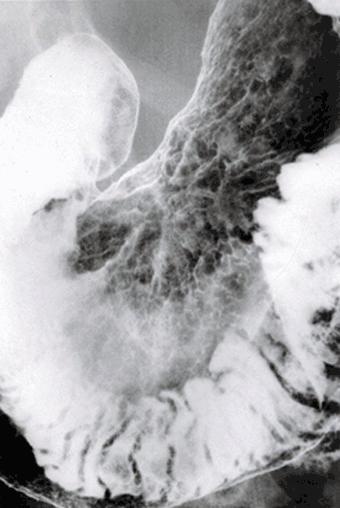

Criteria of Hist.ClassificationMalignant epithelial tumor/Adenocarcinoma

LocationStomach/Angle

Technique, MethodX-ray

Macroscopic TypesType 0/IIc (IIc) Superficial depressed type

Size40 -

Depth of Tumor Invasionmucosa